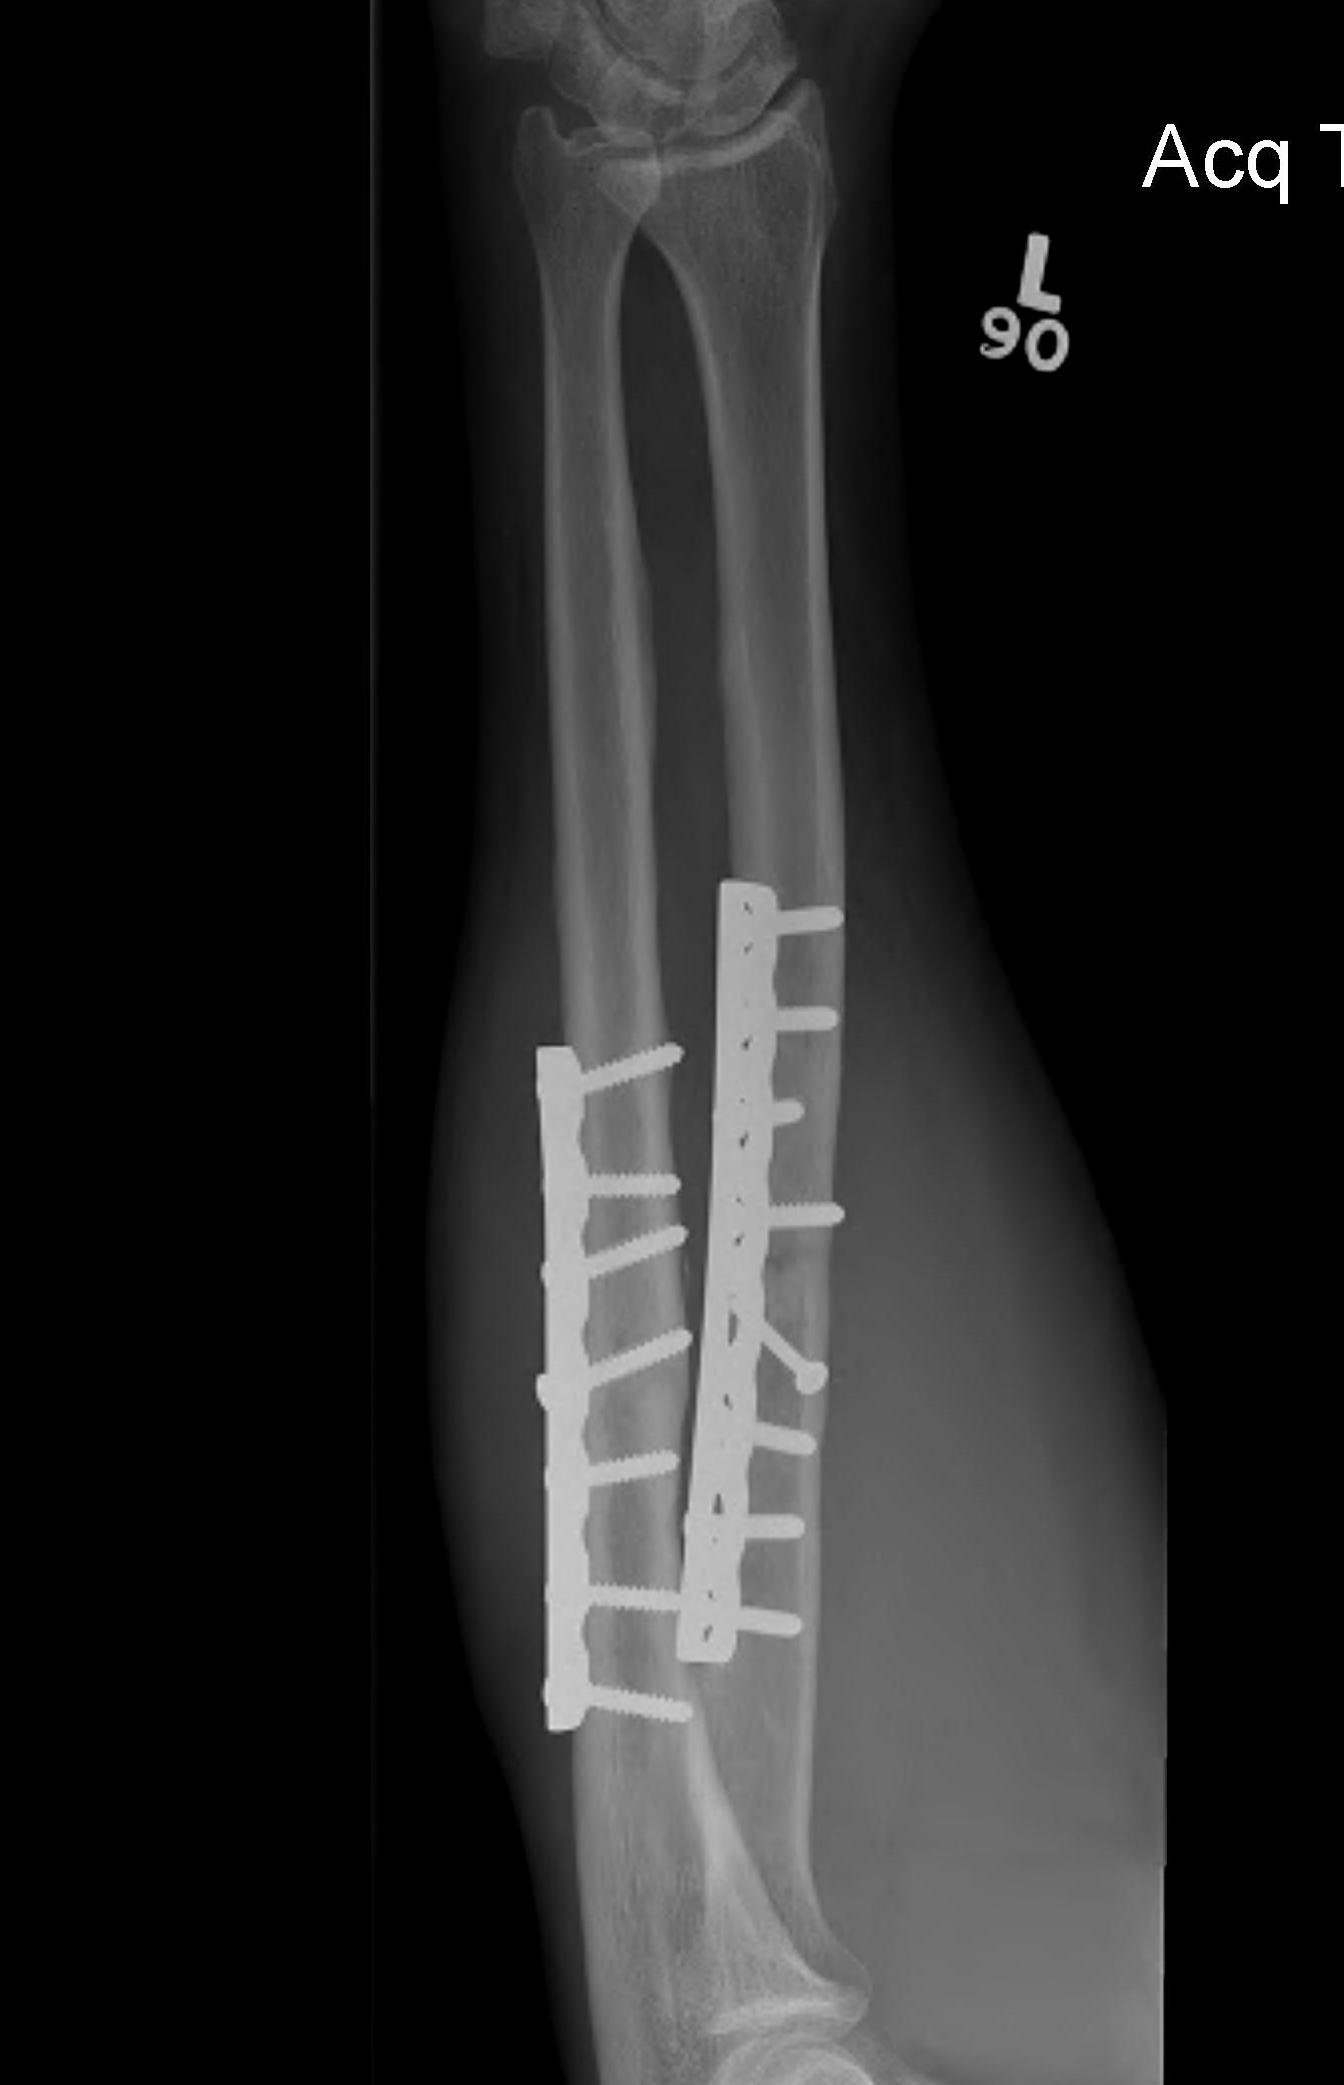

ORIF with plates

ORIF with DCP plates

Fixation with DCP plates